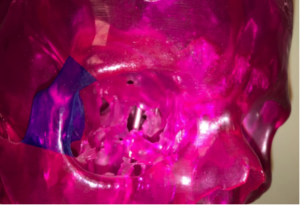

Intraoperatives Bild eines sich bis in den Gehirnschädel ausdehnenden Opticusscheidenmeningeoms vor und nach der Tumorentfernung mit befreitem Sehnerven.

Intraoperativer Aspekt eines Optikusscheidenmeningeoms (Typ 2a) mit Durchwachsen des Meningeoms durch den Sehnervenkanal in den intrakraniellen Raum; Operation über einen Transkranieller operativer Zugang bei einem bis in den Gehirnraum wachsenden Opticusscheidenmeningeom [TU] (linke Seite), nach Tumorentfernung mit entlastetem Sehnerven [SN] und befreitem Hirngefäß [ACI] (rechte Seite).